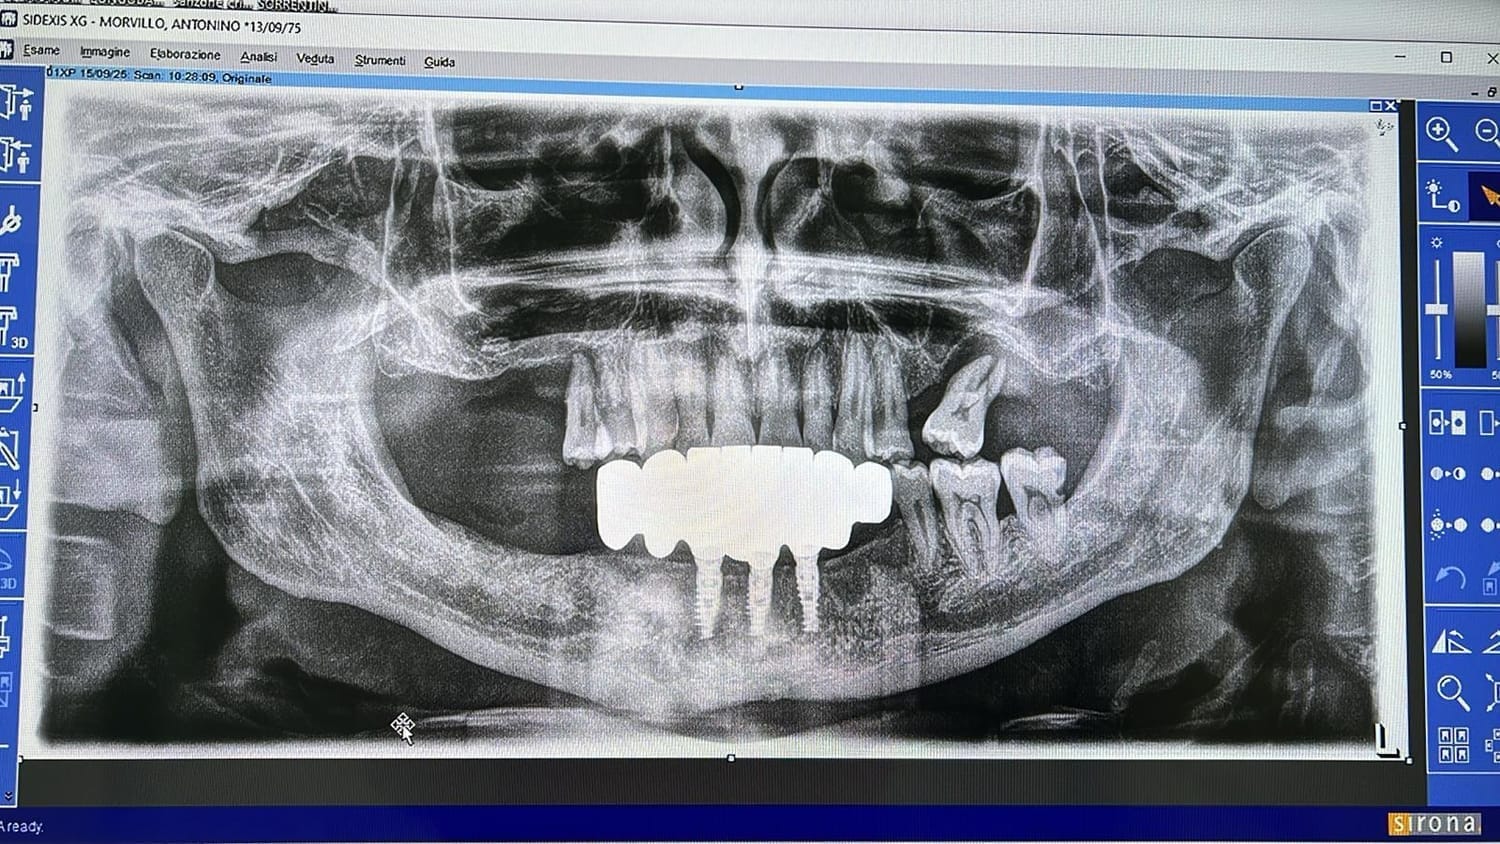

Paziente affetto da atrofia grave con parodontite acuta localizzata.

Caso progettato e realizzato attraverso la tecnica dell'implatologia computer-guidata con impianti short.

Grazie ad una progettazione fatta mediante PC su tac otteniamo preventivamente dove posizionare gli impianti la lunghezza la larghezza e la corretta angolazione di inserimento che ci consente di realizzare le protesi ancora prima di farevlintervento e di evitare tagli e scollamento gengivali che provocano dolore e bruciore riducendo notevolmente itempi di guarigione e i fastidi post intervento